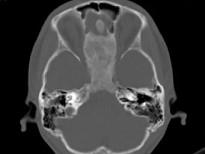

女,17岁,鼻阻塞、头痛两年.如图所示符合筛骨病变最可能的诊断是 ( )

• A.成骨肉瘤

• B.骨瘤

• C.骨化性纤维瘤

• D.软骨瘤

• E.纤维异常增殖症

答案: C